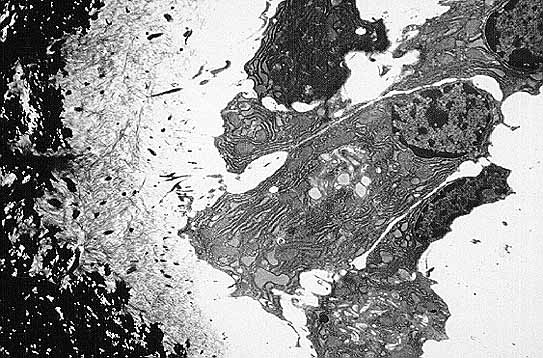

Fig.5: A: Osteoblastos sobre un ribete de osteoide. Obsérvese que el osteoblasto del centro presenta el núcleo en el extremo opuesto a la zona de contacto con el hueso. El osteoide se observa como un material finamente fibrilar de color gris y por debajo del mismo se situa el hueso mineralizado en color negro (Microscopía electrónica x 3400).